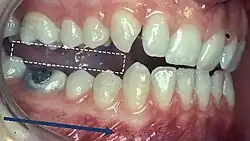

5) Contacts in ICP

Begin by assessing the incisor and molar relationship as described above. Similarly examine the overbite and overjet. An overbite of 3-5mm[2] and an overjet of 2-3mms are considered to be within the range of normal.[13]

To look at the ICP, articulating paper should be placed on the occlusal surface and the patient asked to bite together, which will mark their occlusal contacts. It is best to check these whilst the teeth are dry.

- During ICP, most opposing teeth should be contacting[2]

- Close examination of these contacts marked by the articulating paper help to identify the nature of the tooth contacts

- Good stable contacts often appear as small and not very prominent markings when articulating paper is used and there are multiple contacts on each tooth

- Broad and rubbing contacts identified in ICP may be associated with disturbances in function and may indicate occlusal instability[25]